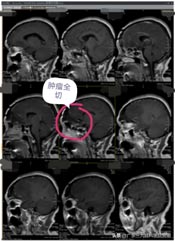

近段时间来,林阿姨头痛越来越重,偶尔还会出现小便失禁,林阿姨这才有所警觉。在医院头颅CT检查,显示:前颅底巨大占位,考虑脑膜瘤可能性大。林阿姨吓坏了,半辈子都平平安安,想不到脑子里居然有这么大的一个肿瘤。

孩子们也非常担忧,通过四处打听,林阿姨来到了广东三九脑科医院。进一步影像检查也提示是:前颅窝底巨大占位性病变,考虑脑膜瘤可能性大。

肿瘤体积巨大,占位明显,医院副院长、神经外五科主任鲁明和团队一起经过讨论,快速制定了安全且风险较小的手术方案,术中需要避开重要血管,尽最大可能全切除肿瘤。术前进行全脑血管造影,影像显示:前颅底异常染色,呈类圆形,肿瘤主要是由右侧脑膜中动脉前支、右侧眼动脉分支参与供血;决定先行肿瘤栓塞术,术后加压包扎送病人至手术室,行“前颅底巨大脑膜瘤切除术”。肿瘤周围血管丰富,已侵犯重要神经;导航准确定位,显微镜下见肿瘤起源于大脑镰及前颅底,阻断肿瘤血供后,先钨刀切除左侧额部部分肿瘤,再超吸切进行瘤内减压,最终镜下将肿瘤切除干净。